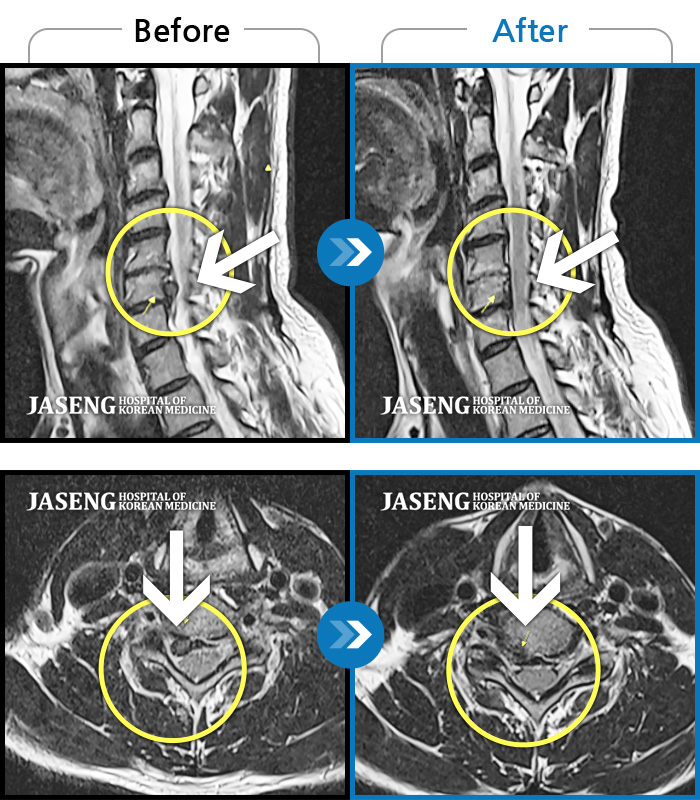

MRI 치료사례

목디스크로 인한 목통증 및 간헐적 손바닥 저림 증상